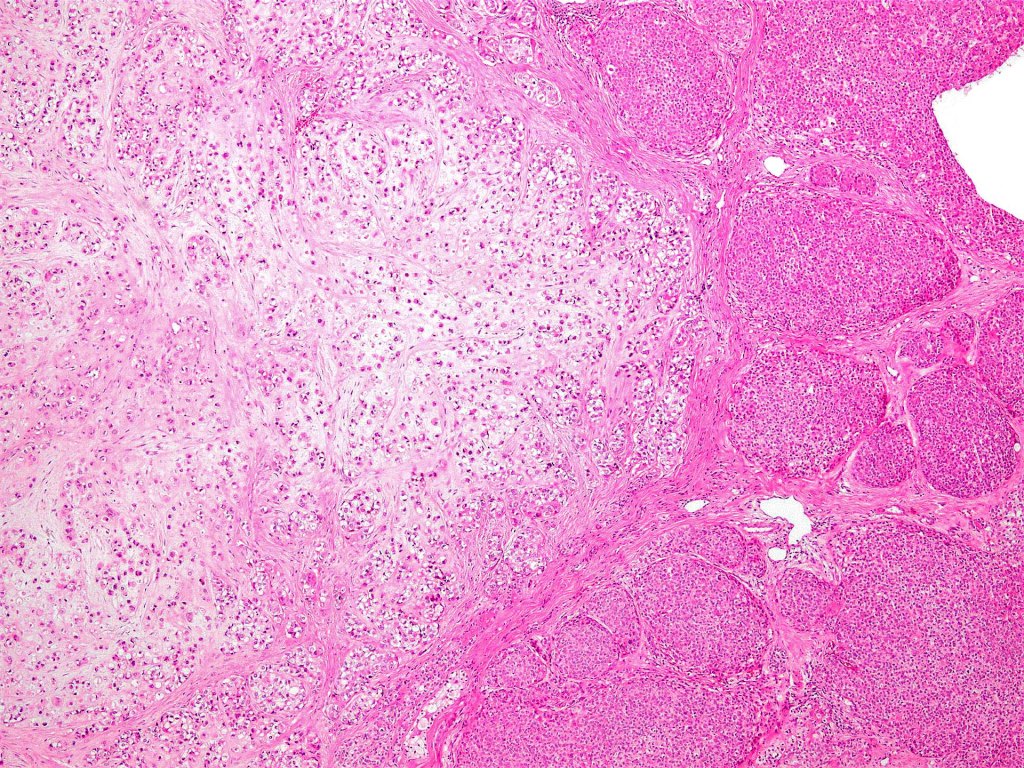

•Biphasic tumor

•Admixture of squamous carcinoma & pleomorphic spindled cell, osteoid, chondroid, MFH-like +/- osteoclast-like giant cells & rarely, smooth muscle, skeletal muscle, myofibroblastic or angiosarcomatous elements